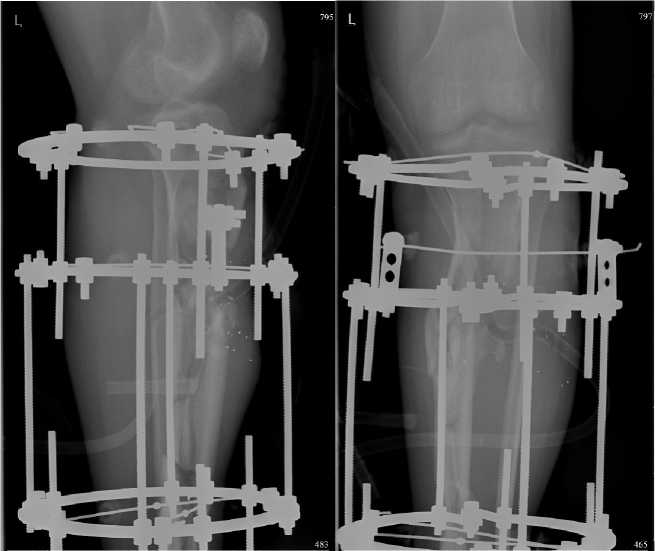

Рисунок 5. На рентгенограммах левой голени в двух проекциях определяется многооскольчатый перелом проксимальной и средней трети диафиза левой большеберцовой кости, осложненный остеомиелитом в условиях металлоостеосинтеза аппаратом Илизарова, дренирования мягких тканей

Figure 5. Radiographs of the left leg in two projections show a multi-fragmentary fracture of the proximal and middle third of the diaphysis of the left tibia, complicated by osteomyelitis in the conditions of metal osteosynthesis with the Ilizarov apparatus, drainage of soft tissues